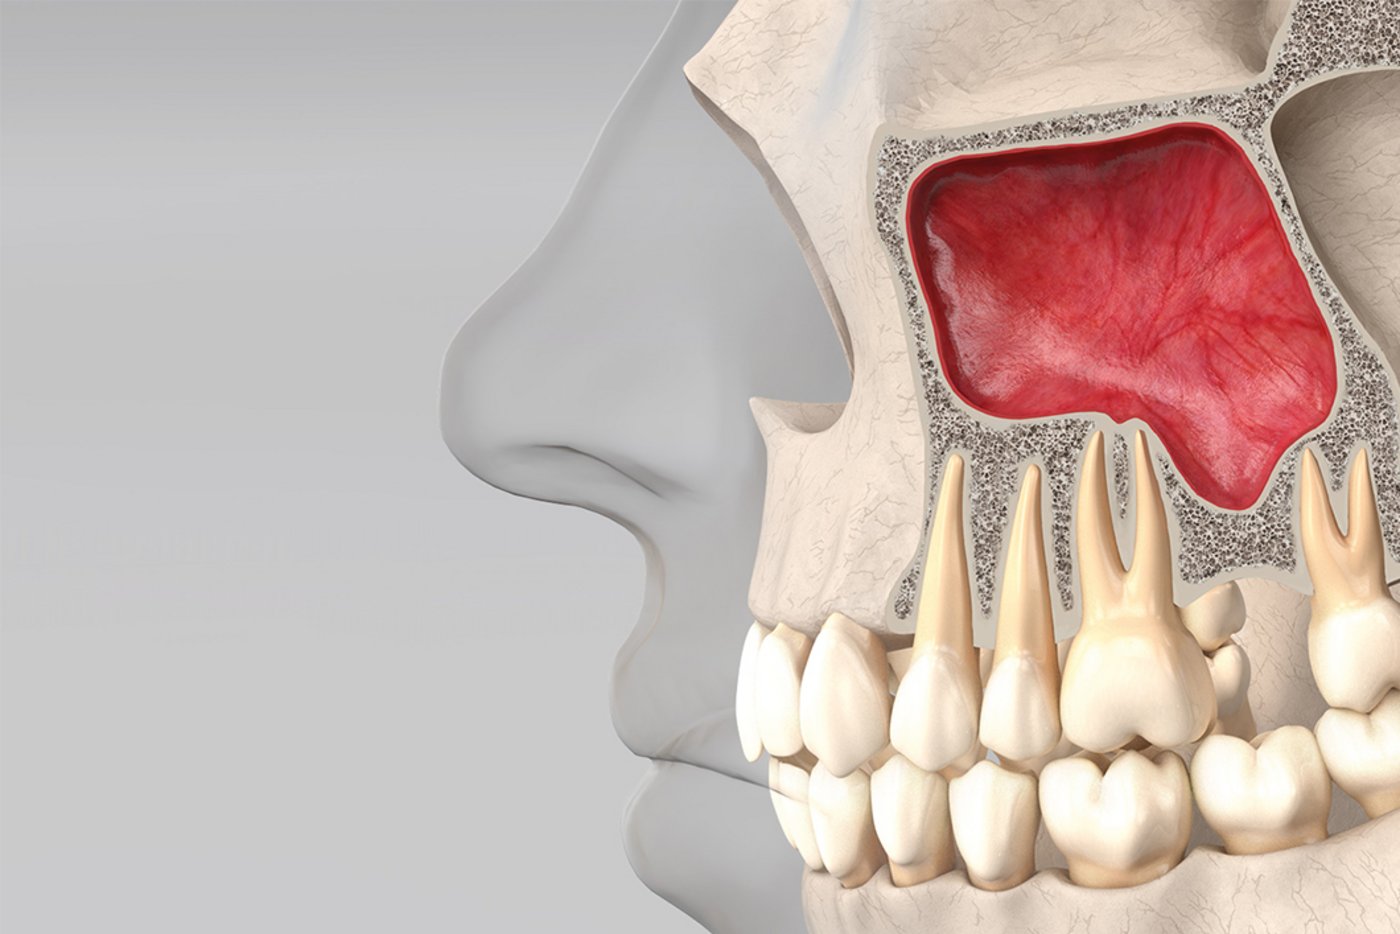

Geistlich Usa Crestal Sinus Floor Elevation Background this study evaluated the clinical and radiographic outcomes of using demineralized dentin matrix (ddm) as a graft material at the implant apex during crestal sinus floor elevation. we hypothesized that ddm would promote predictable bone regeneration at the sinus floor and facilitate implant stability with minimal surgical morbidity. methods a retrospective analysis was performed on. This clinical case, with 12 month follow up, showed the employment of geistlich bio oss® and geistlich bio gide® in sinus floor elevation for the purpose of rehabilitation with dental implants. No significant sinus complications or graft failures occurred. within the limitations of this retrospective study, crestal sinus elevation with ddm grafting at the implant apex proved to be a safe and effective minimally invasive technique, consistently yielding bone regeneration and excellent implant survival in the posterior maxilla. pmid. This study encourages the crestal approach to sinus elevation, even in patients with less than 4 mm of residual bone height. the postoperative radiograph and the three year follow up showed a significant increase in vertical bone height that remained stable over time. This technique involves accessing the sinus through the alveolar ridge at the intended implant site. a small opening is created in the crestal bone, and specialized instruments are used to gently apply controlled vertical pressure, fracturing the sinus floor while preserving membrane integrity. Dr. rui figueiredo places the implant before completely filling the sinus with geistlich bio oss® granules (delivered by the geistlich bio oss pen®).

Geistlich Usa Crestal Sinus Floor Elevation No significant sinus complications or graft failures occurred. within the limitations of this retrospective study, crestal sinus elevation with ddm grafting at the implant apex proved to be a safe and effective minimally invasive technique, consistently yielding bone regeneration and excellent implant survival in the posterior maxilla. pmid. This study encourages the crestal approach to sinus elevation, even in patients with less than 4 mm of residual bone height. the postoperative radiograph and the three year follow up showed a significant increase in vertical bone height that remained stable over time. This technique involves accessing the sinus through the alveolar ridge at the intended implant site. a small opening is created in the crestal bone, and specialized instruments are used to gently apply controlled vertical pressure, fracturing the sinus floor while preserving membrane integrity. Dr. rui figueiredo places the implant before completely filling the sinus with geistlich bio oss® granules (delivered by the geistlich bio oss pen®).